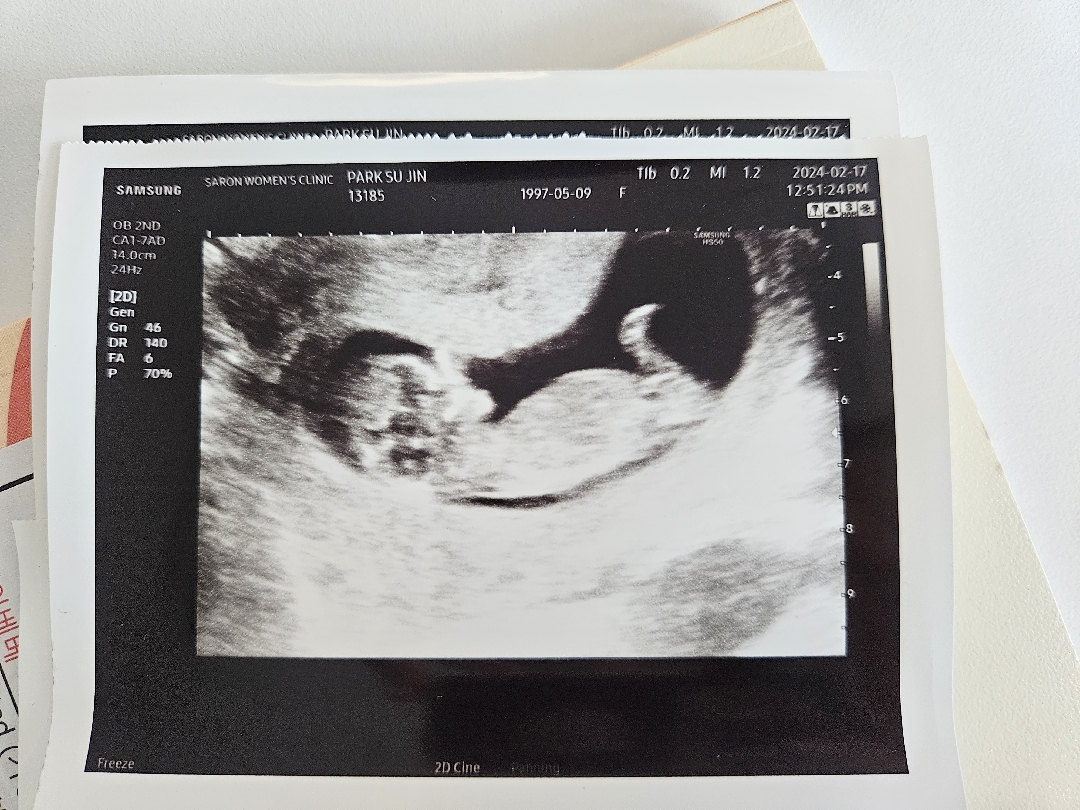

11주 4일차 아기 각도!

안녕하세요! 오늘 복부 초음차 처음했는데 혹시 이 시기도 각도로 성별 유추 가능할까요..?!

사진상으로는 각도가 안보여요ㅜ